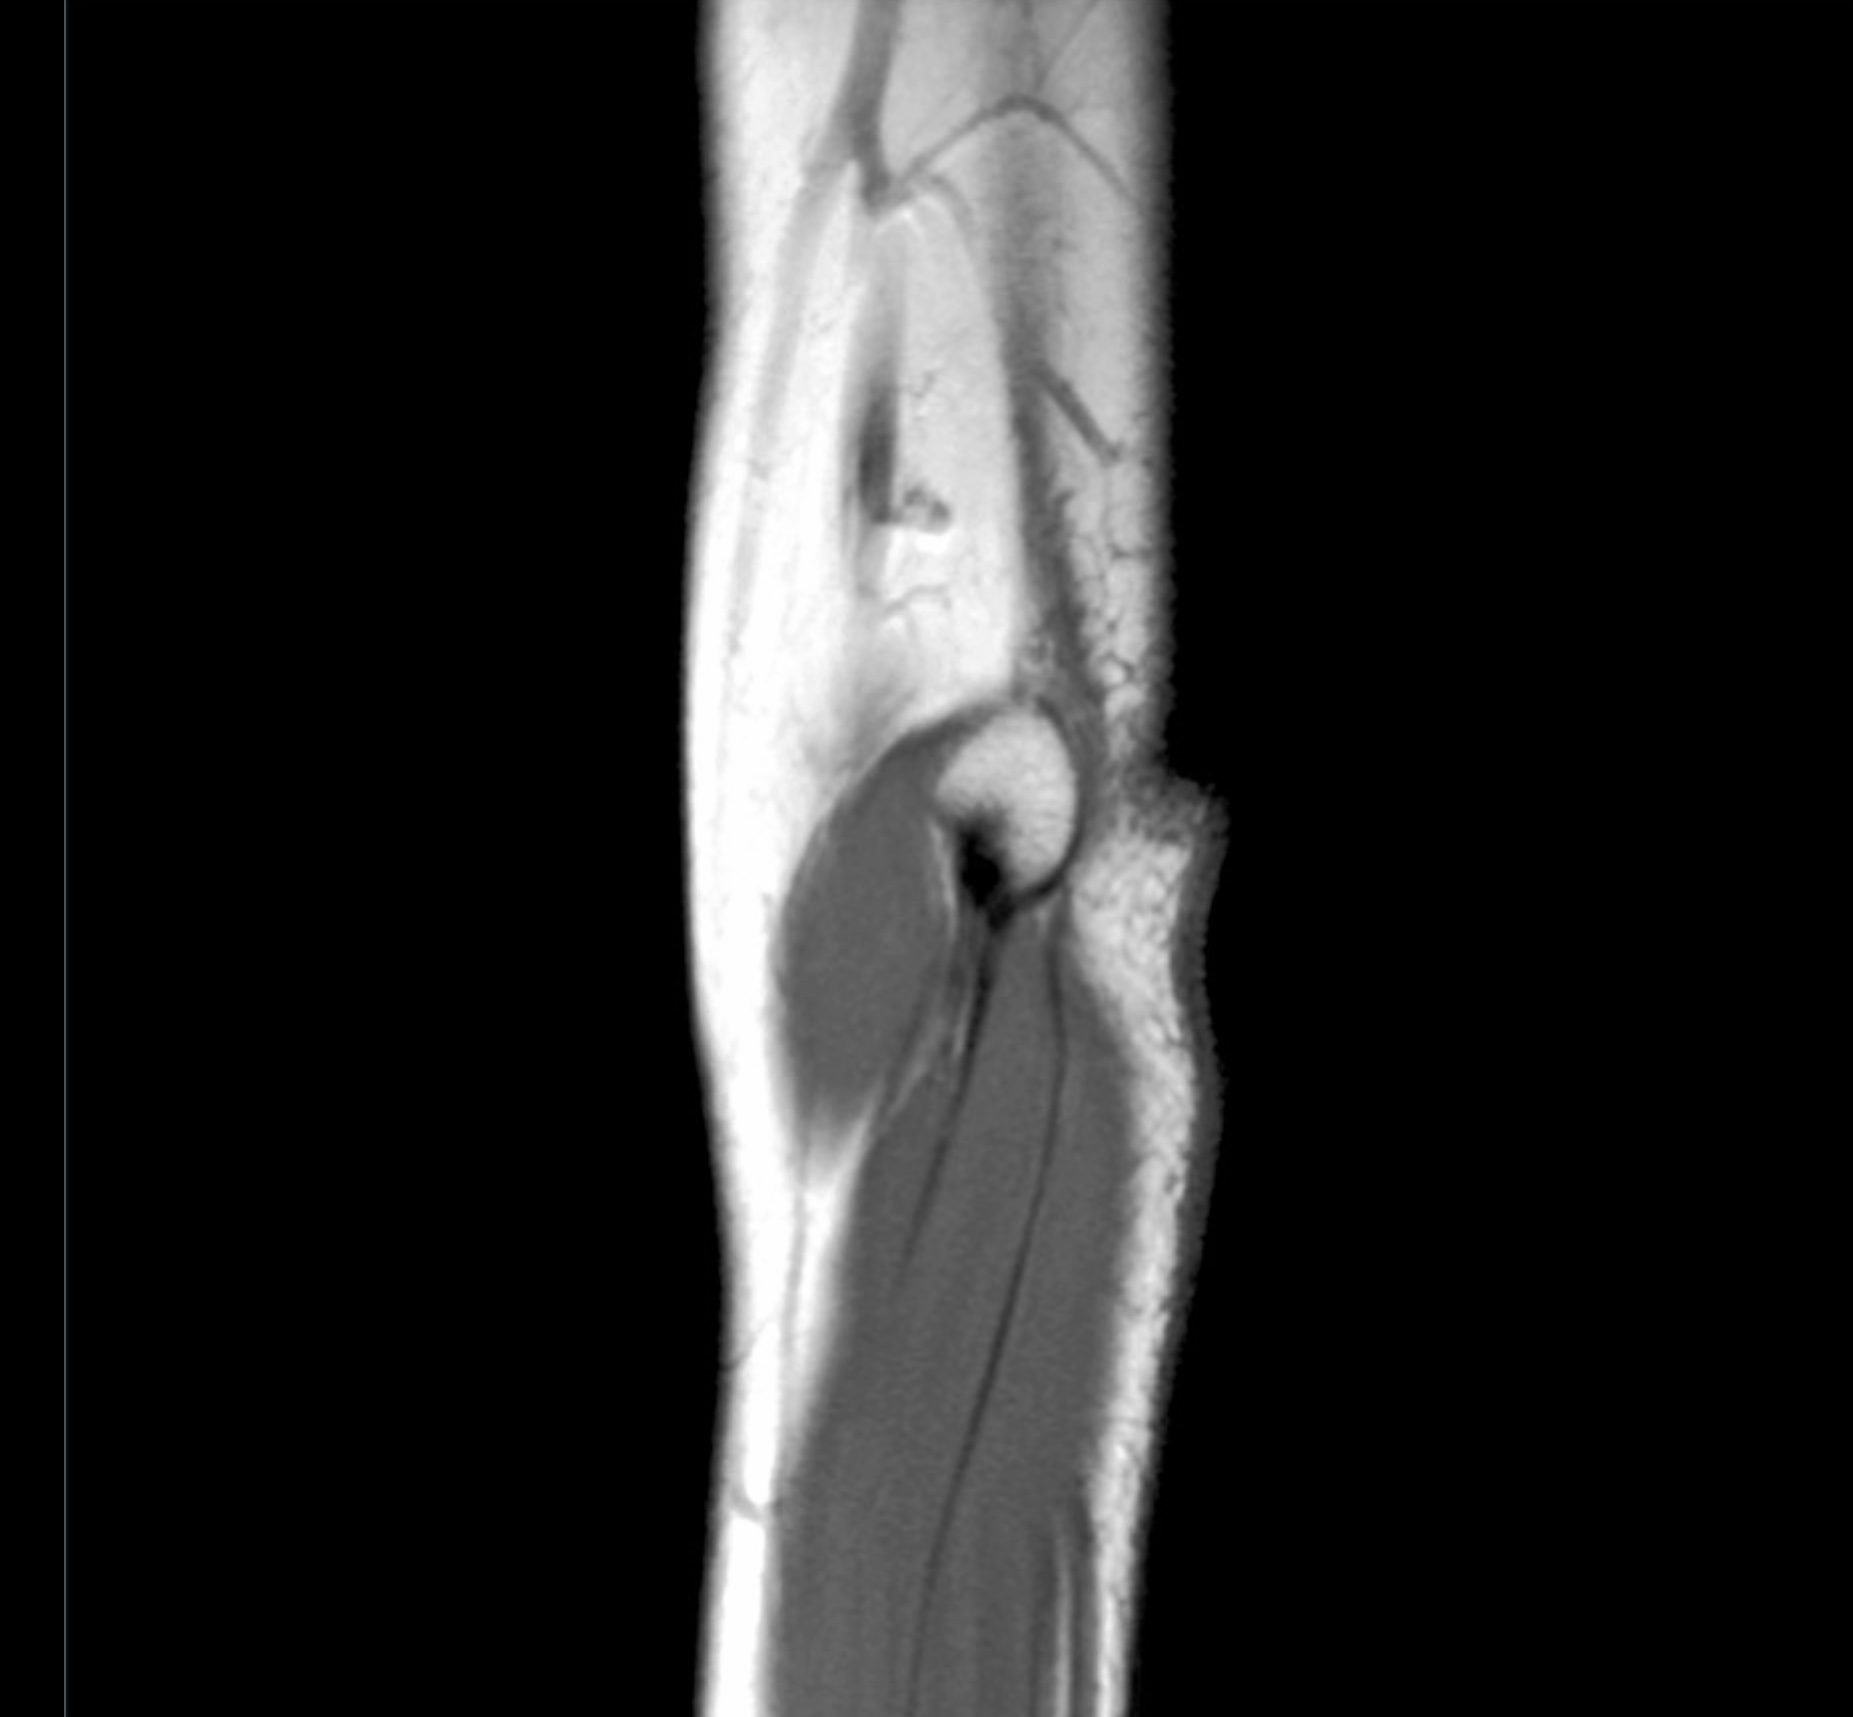

2. A 27-year old patient suffers a humeral shaft fracture at the radial groove. Discuss the anatomy of the posterior compartment of the arm, including boundaries, contents, musculature, vascular supply, innervation, lymphatics and relationships. Differentiate between motor deficits of posterior arm and posterior forearm musculature relative to branching of the radial nerve superior and inferior to the radial groove.

3. The elbow joint consists of three joints: the humeroradial, humeroulnar, and proximal radioulnar joints. Review the anatomy of the elbow joint. Include bones, articulations, ligaments, capsules, movements and limitations of movements. Relate the anatomy of the medial ulnar collateral ligament to Tommy John surgery.